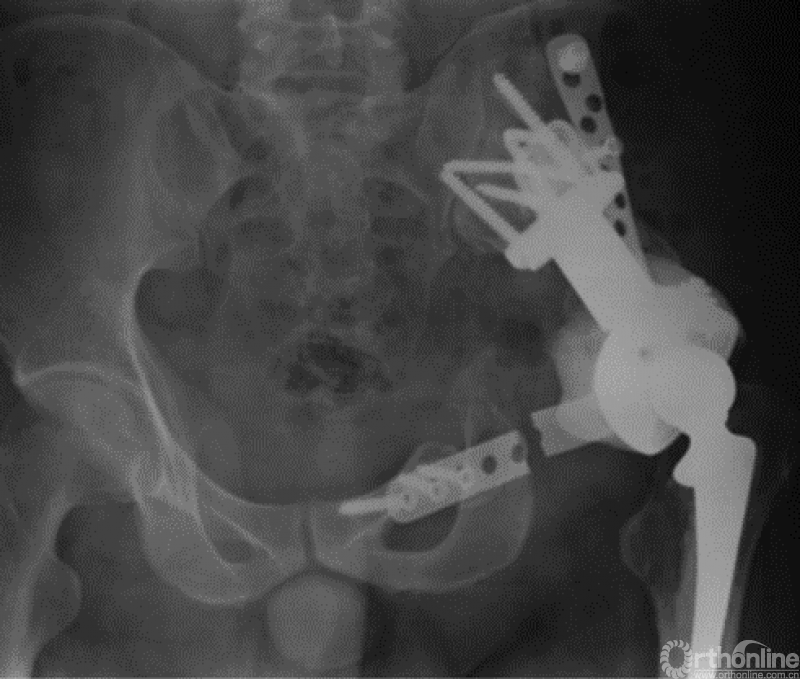

自1971年第一例定制化半骨盆假体投入临床应用起,其设计理念及方法一直在快速发展[16]。随着3D打印技术的应用以及假体设计进一步改良,定制化半骨盆假体的预后已经得到了长足进步[17-26](图4)。

图4 3D打印定制化半骨盆假体